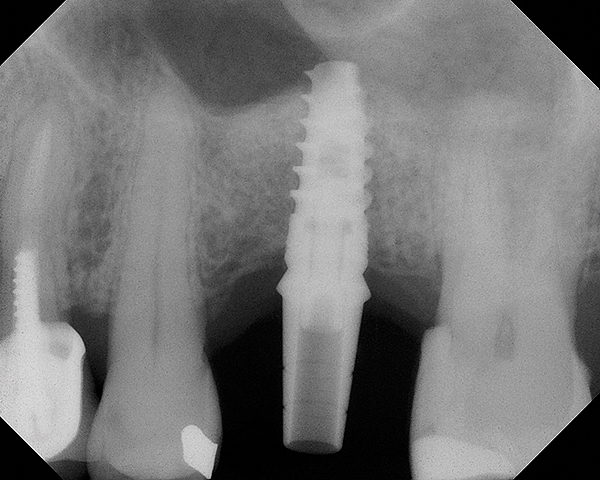

Because the bone grafting materials used in this technique need physical stability during healing to support the raised membrane, there is a high probability that significant shrinkage of the graft will occur as it heals and matures if only non-demineralized material is used. For these reasons, a composite graft using calcium sulfate, DFDBA, and mineralized particulate bone is used. A 50:50 mixture by volume of mineralized bone grafting material and DFDBA is used, to which approximately 40% calcium sulfate by volume is added. A higher percentage of calcium sulfate is used relative to that described for composite grafting in other uses, because some of the calcium sulfate will wash out during bone packing. Another advantage to this composite graft is that it is not as radiopaque as a purely mineralized graft. This allows radiographic monitoring of the bone healing around the implant, which can be used to time abutment placement on the implant. This is demonstrated in Figure 4 and Figure 5, which are radiographs taken on the day of the initial surgery showing the radiographic appearance of the composite graft, implant, and graft, and in Figure 6, a 5-month postoperative radiograph with the abutment in place. The old floor of the sinus is indistinguishable from the area of new bone. Figure 7 shows a CBCT scan (Carestream Dental, www.carestreamdental.com) taken at 4 months with the old floor of the sinus indistinguishable from the new bone formed.

Fig 4. Radiograph showing the sinus membrane being elevated about 8 mm supported by a composite bone graft that is partially radiolucent in the No. 14 position.

Figure 4

Fig 5. Radiograph of implant No. 14 and graft in place, day of placement.

Figure 5

Fig 6. 5-month postoperative radiograph showing good healing of the augmented bone with the old floor of the sinus indistinguishable.

Figure 6

Fig 7. 4-month CBCT scan (Kodak 9000D) of implant No. 14.

Figure 7